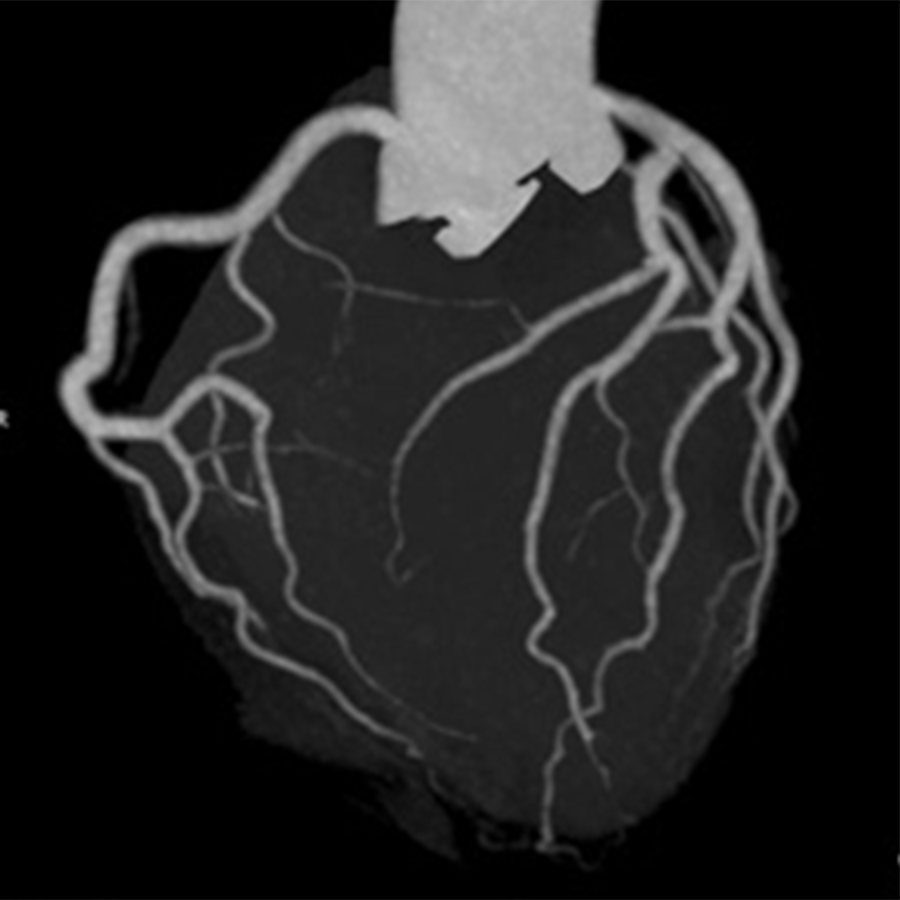

冠動脈CT導入のお知らせ

原土井病院では、7月27日(月)より冠動脈CT(キャノン社製80列CT)を導入いたします。冠動脈CTは、心臓カテーテル検査とは違い、低侵襲で冠動脈病変の性状を詳細に評価することが可能です。